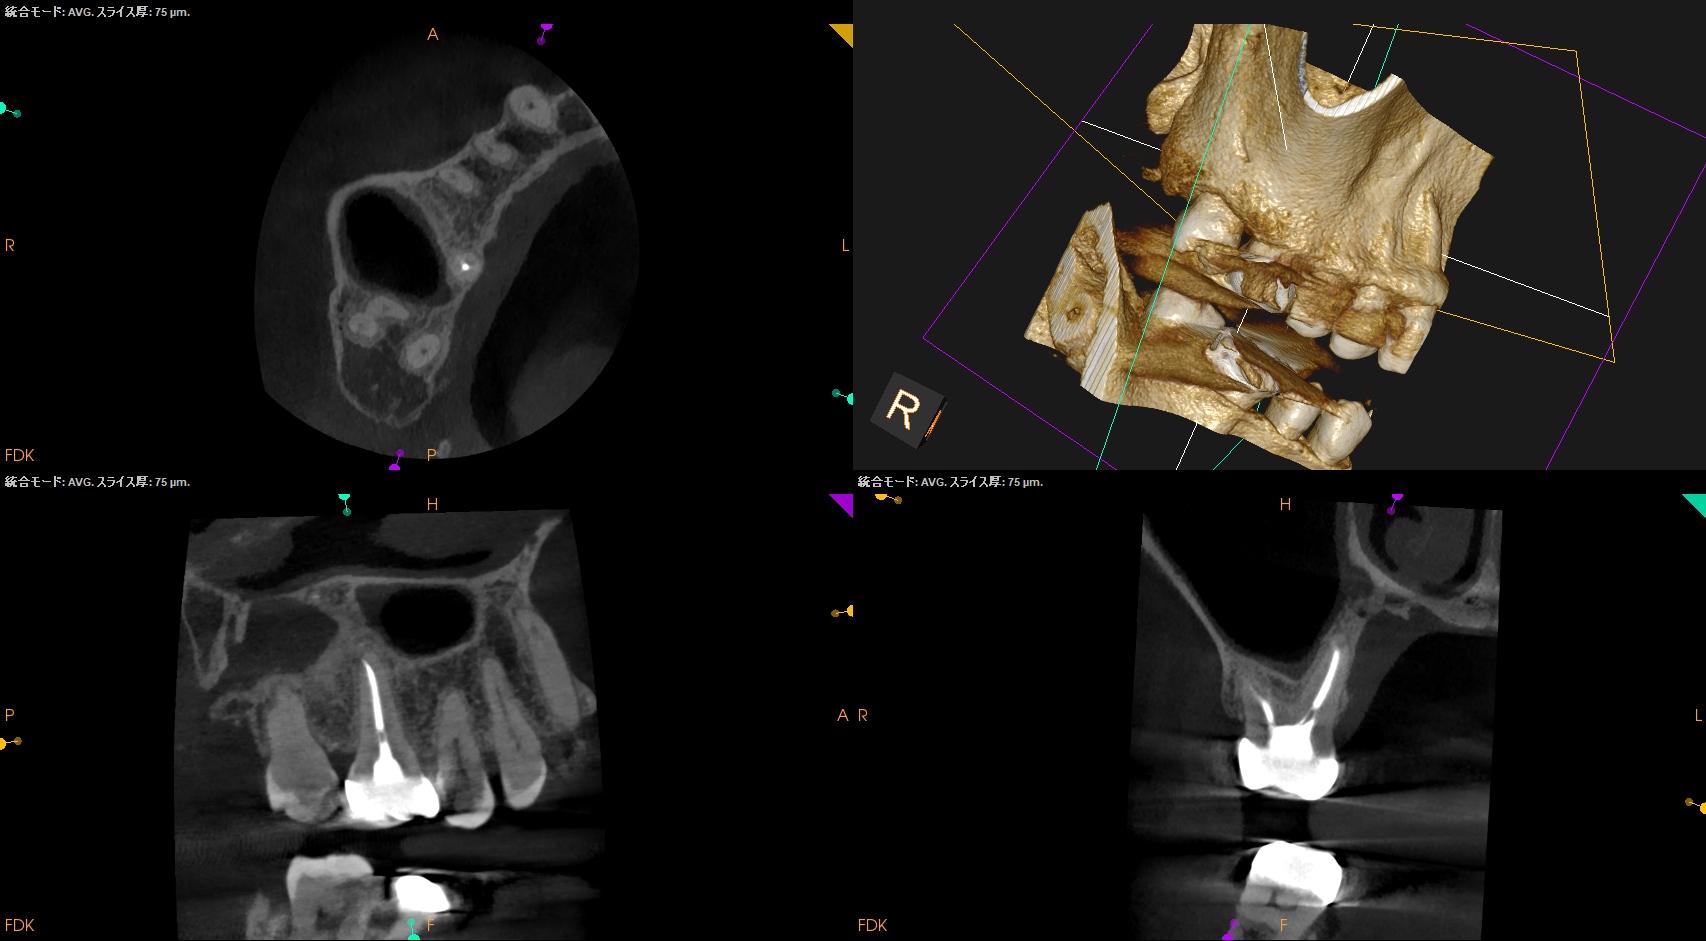

PA, CBCTも撮影した。

MB

DB

P

B

初診時と比較した。

臨床症状、Sinus tractは消失し完治した。